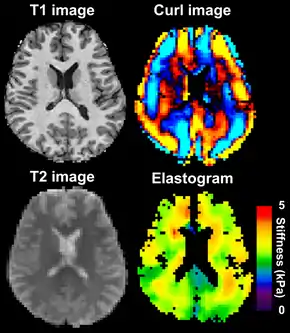

![]() Magnetic resonance elastography of the brain. A T1 weighted anatomical image is shown in the top-left, and the corresponding T2 weighted image from the MRE data is shown in the bottom-left. The wave image used to make the elastogram is shown in the top-right, and the resulting elastogram is in the bottom-right. | |

MRE is conducted in three steps: first, a mechanical vibrator is used on the surface of the patient's body to generate shear waves that travel into the patient's deeper tissues; second, an MRI acquisition sequence measures the propagation and velocity of the waves; and finally this information is processed by an inversion algorithm to quantitatively infer and map tissue stiffness in 3-D.[2][3] This stiffness map is called an elastogram, and is the final output of MRE, along with conventional 3-D MRI images as shown on the right.[2]